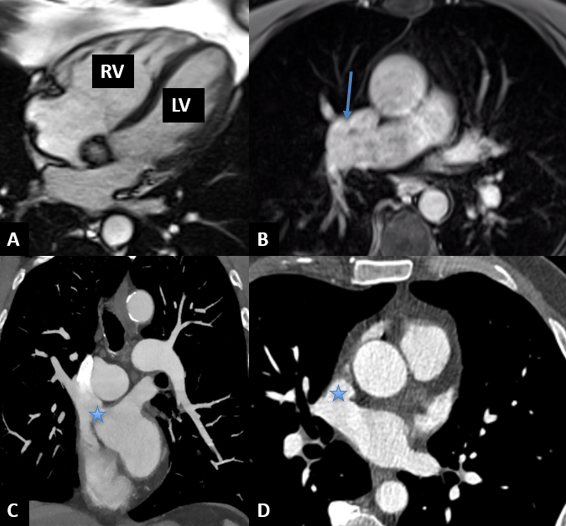

Given the right ventricular dilation shown in the TTE, a cardiac MRI was performed. The MRI showed moderate RV dilation with evidence of partial anomalous pulmonary venous drainage (PAPVR), with the right upper and middle pulmonary veins draining into the superior vena cava (SVC). There was evidence of significant left-to-right shunt with a Qp/Qs of 1.8. Cardiac computed tomography angiogram (CTA) showed a large superior sinus venosus atrial septal defect (SVASD) between the wall of the SVC, and the right middle pulmonary vein measuring 2.6 cm in the superior-inferior dimension and 1.7 cm in the right-left dimension. Right upper and middle pulmonary veins drained into the SVC just above the defect (Figure 1, Video 1). There was normal drainage of the remaining pulmonary veins.

Upon review of the CTA, the defect appeared amenable to percutaneous closure with a covered stent in the SVC. The patient was counseled on options for closure, including surgical repair and a covered stent. Intraoperative TTE again showed the SVASD and anomalous pulmonary venous drainage. Two covered stents were placed; the first stent successfully routed the anomalous veins posteriorly across the defect to the left atrium without pulmonary venous obstruction (Video 2). There was a small residual ASD (4 mm) at the inferior portion of the stent, for which a second stent was placed. There was no residual left-to-right flow after the second stent and no pulmonary venous obstruction (Figure 2; Videos 3 and 4). At 1-month follow-up, the patient was asymptomatic and TTE demonstrated a significant decrease in right ventricular size.